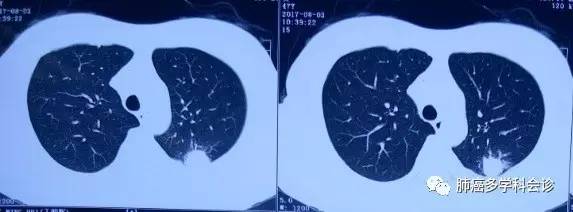

患者丁MH,女,47岁。2017年4月因咳痰、胸闷在当地医院行CT检查,发现左肺上叶占位性病变、左侧大量胸腔积液、纵膈及左侧腋窝淋巴结肿大。超声提示双侧颈部异常淋巴结,考虑转移。

2017.06.08 复查CT:左肺肿块稍缩小,左侧胸腔积液量增多,胸骨、左侧肱骨头、部分胸、腰椎骨质改变,考虑骨转移。SPECT进一步证实全身多发骨转移;

2017.08复查CT:较前变化不大。脑MRI未见转移灶。

2017.08.06复查CT如下: